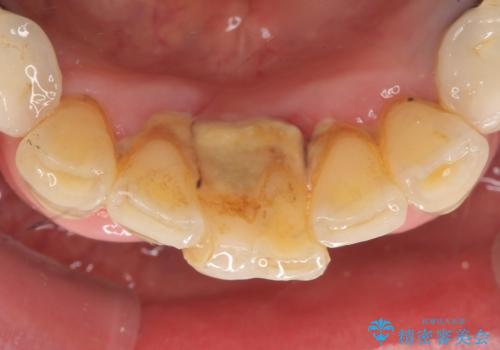

前歯が抜けそう ブリッジできれいに 70代女性

- 上下の前歯が抜けそうだとのことで来院されました。

精査したところ、動揺の著しい上下の前歯は重度の歯周病により保存不可能と判断しました。

ブリッジ、インプラント、義歯の選択肢の中で上下前歯ともにブリッジをご希望されました。